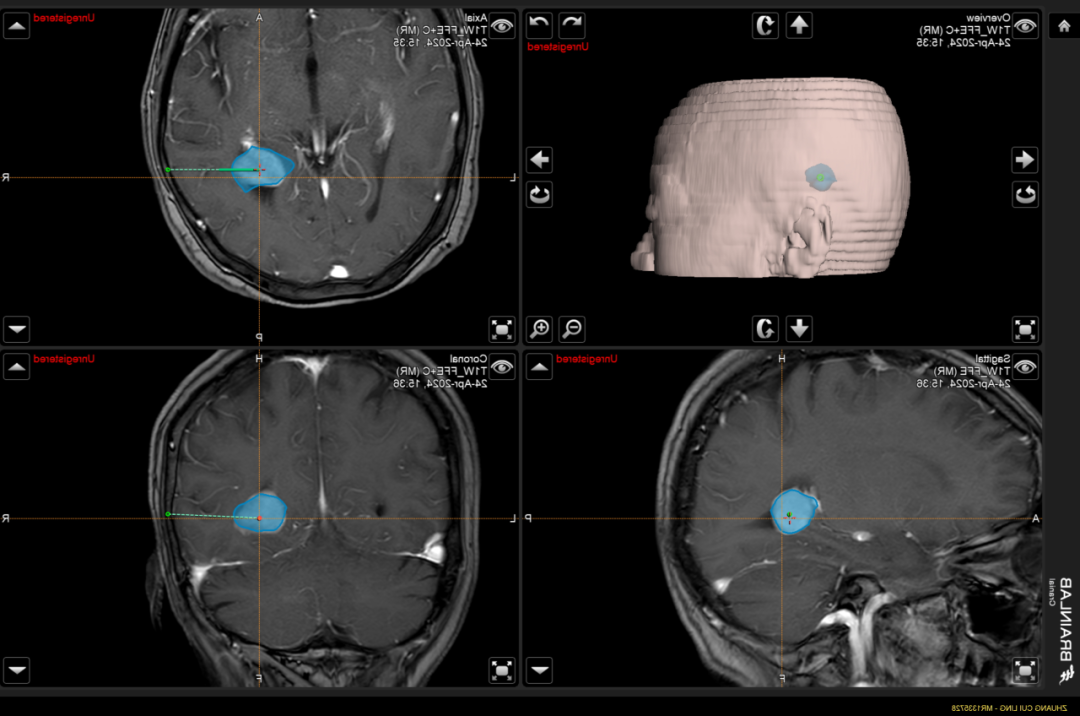

▲患者头颅MR增强

考虑脑膜瘤可能!

入院后,神经外科主任王文华立刻组织术前讨论并表示:该患者肿瘤位于三角区,位置较深,肿瘤大小2.2cm*1.6cm,肿瘤周围血管、神经丰富,手术难度较大,传统开颅肿瘤切除术中出血多,肿瘤定位困难,对血管神经的破坏较大。市中医医院引进的术中导航系统可以精准定位肿瘤,计算最优路径,减少脑组织的损伤,减少术中出血。

▲术中神经导航模拟肿瘤位置,精准定位,计算最优路径

经神经导航的辅助,选取微创小切口,完整切除肿瘤,术中出血少,对功能区保护满意。